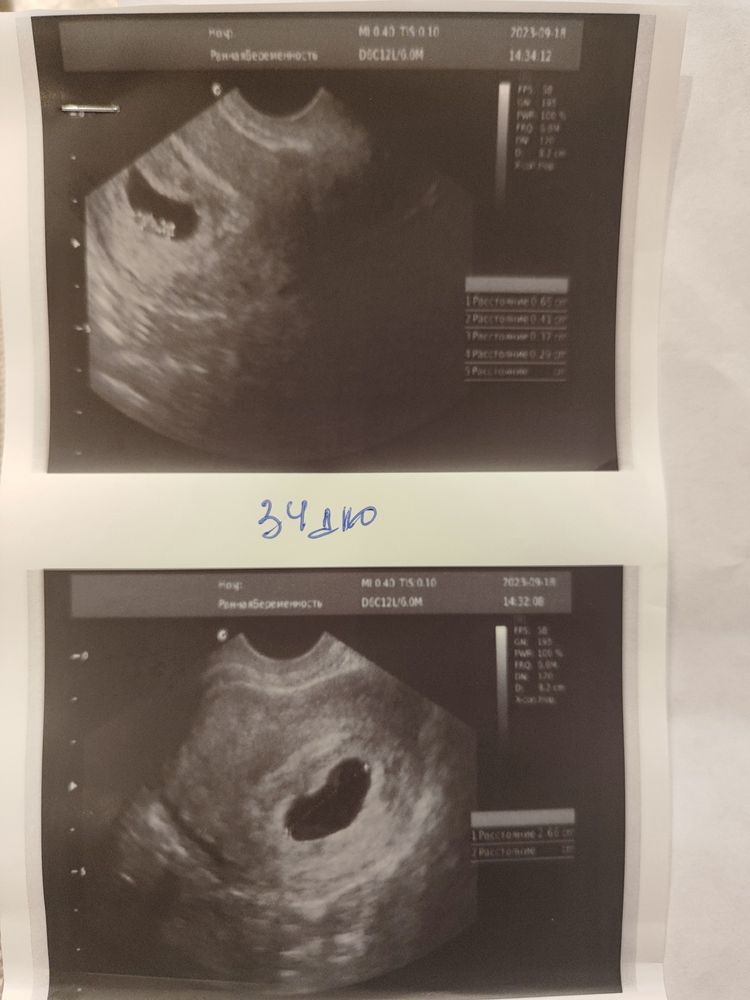

Была на УЗИ:

34 дпо- (6.4 нед) эмбриона нет, жм+(сомневается врач) ПЯ 20.0 по фото видно что округляется (ХГЧ 60тыс).

Прикрепляю УЗИ 32 дпо и 34 дпо-... Может кто-то что-то поймет.